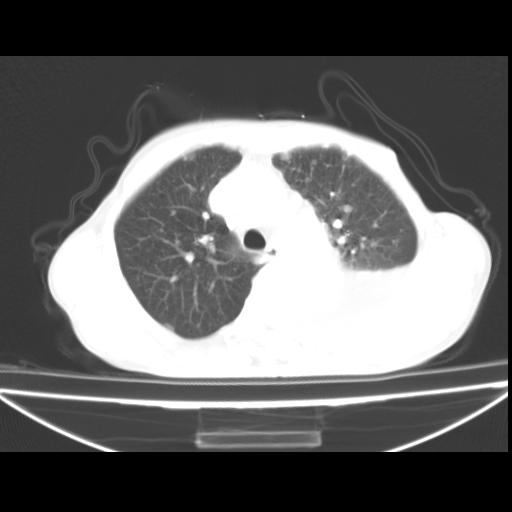

以下是引用随光逐影在2010-3-24 19:15:00的发言:[br]结合病史,考虑双肺及纵隔淋巴结多发转移、左侧胸膜转移并左侧大量胸水,左下肺膨胀不全。

以下是引用zxl51642在2010-3-24 18:49:00的发言:[br]结合乳腺癌术后病史,考虑双肺及纵隔淋巴结多发转移、左侧胸膜转移并左侧大量胸水、左下肺膨胀不全。